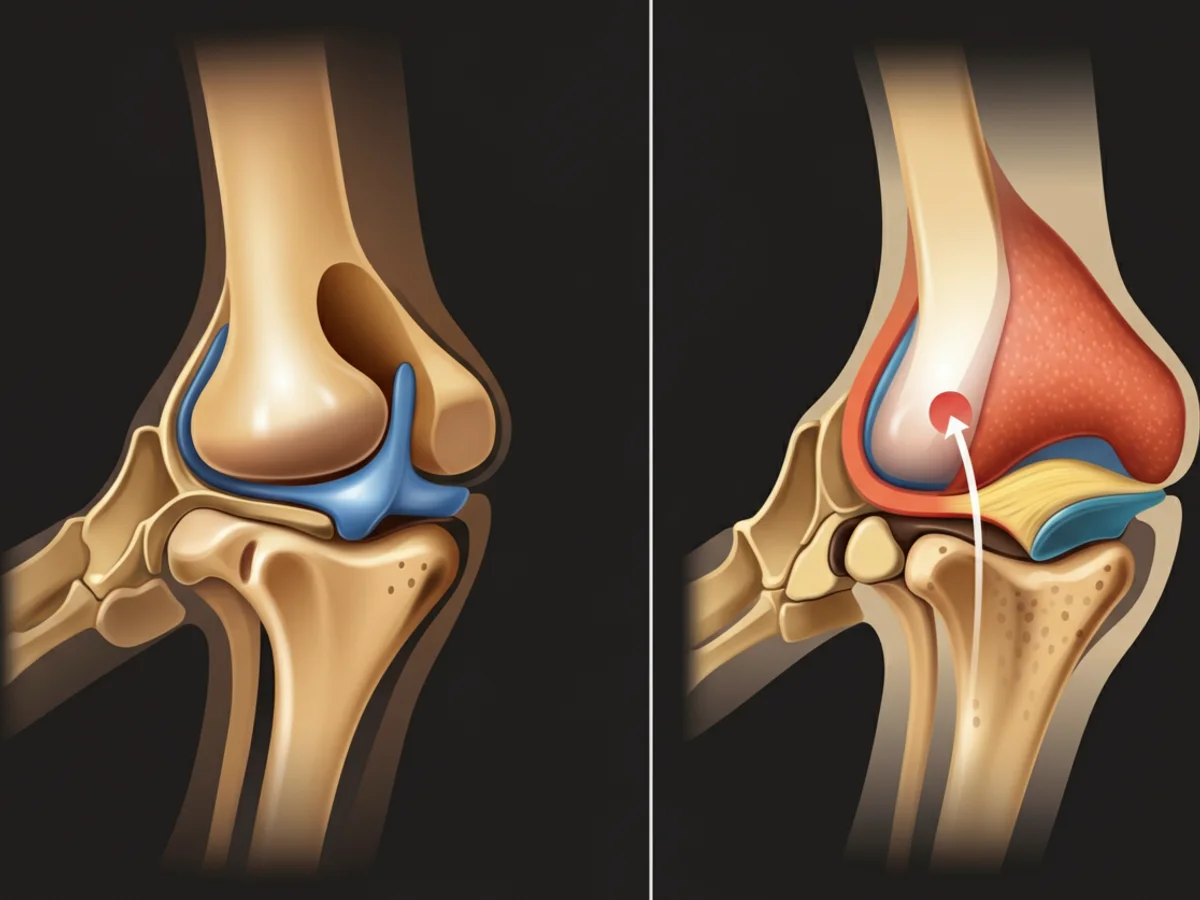

Arthrose ist eine **chronische Gelenkerkrankung** bei Hunden, die vor allem ältere Tiere betrifft, aber auch jüngere Hunde betreffen kann, insbesondere wenn sie Übergewicht haben oder bereits Gelenkverletzungen erlitten haben. **Arthrose** führt zu **Gelenkschmerzen** und **Bewegungseinschränkungen**, was die Lebensqualität Ihres Hundes erheblich beeinträchtigen kann. Eine rechtzeitige Diagnose und eine individuell abgestimmte Behandlung können Schmerzen lindern und die Gelenkfunktion erhalten. Es ist für Tierbesitzer entscheidend, die Symptome zu erkennen und entsprechend zu handeln, um das Wohlbefinden ihres Vierbeiners zu gewährleisten.

Arthrose bei Hunden tritt häufig infolge von:

Zur Diagnose von Arthrose wird der Tierarzt zunächst eine gründliche körperliche Untersuchung Ihres Hundes durchführen, um den Bewegungsumfang und eventuelle Schmerzreaktionen zu beurteilen. Oft sind Röntgenaufnahmen erforderlich, um den Zustand der Gelenke genauer zu untersuchen. In einigen Fällen kann auch eine Ultraschalluntersuchung oder MRT notwendig sein. Diese Tests helfen, andere mögliche Ursachen für die Symptome auszuschließen und die Schwere der Arthrose zu bestimmen.